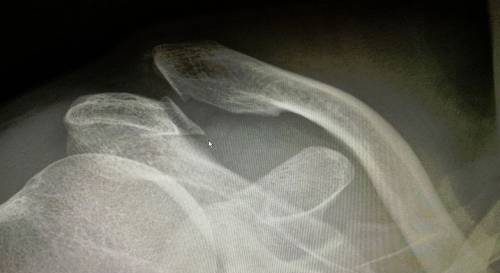

При необходимости пострадавшему назначается рентгенологическое исследование в передней и задней проекциях. После анализа результатов врач подтверждает или уточняет диагноз.

Рентгенография особенно важна для различения полного вывиха от частичного. Специалист сравнивает снимки поврежденной и здоровой стороны. Также рентгеновские снимки необходимы для выявления дополнительных переломов.